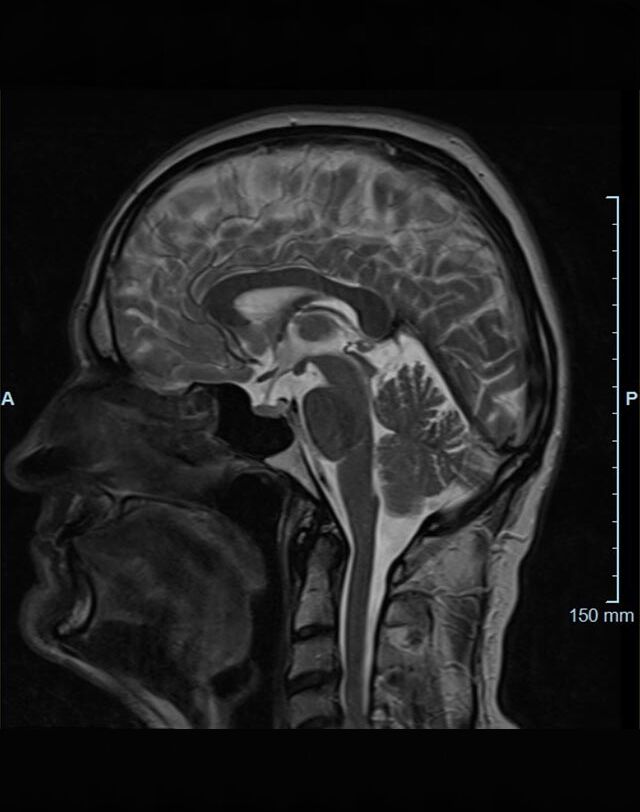

Im Magnetresonanztomographen liegt die zu untersuchende Person in einem starken, homogenen Magnetfeld. Dieses Magnetfeld bewirkt eine gemeinsame Ausrichtung der Wasserstoffprotonen im Körper entlang der Längsachse des Magnetfeldes. Wird nun diesen Teilchen Energie in Form von Radiowellen in einer genau abgegrenzten Frequenz zugeführt, so werden sie aus ihrer ursprünglichen Orientierung abgelenkt.

Die zugeführte Energie wird in gewebespezifischer Weise wieder abgegeben. Ein hochempfindliches Computersystem misst die unterschiedliche Energieabgabe und setzt sie in Bildinformationen um. Jede Körperregion kann somit durch Schnittbilder in allen Raumebenen oder durch dreidimensionale Rekonstruktionen mit einem exzellenten Weichteilkontrast dargestellt werden. Es besteht keine Belastung durch Röntgenstrahlen.

Kopf/Hals

• akute Schlaganfalldiagnostik und chronische Durchblutungsstörungen

• entzündliche Prozesse des Gehirns oder der Gesichtsweichteile

• Tumore

• Abklärung Schwindel, zentrale Sehstörung, Kopfschmerz

• Metastasenverdacht

• Multiple Sklerose

• Abklärung Hirnnerven, Schädelbasis inkl. Hypophyse

• Abklärung Kleinhirn, Hirnstamm, Halsmark